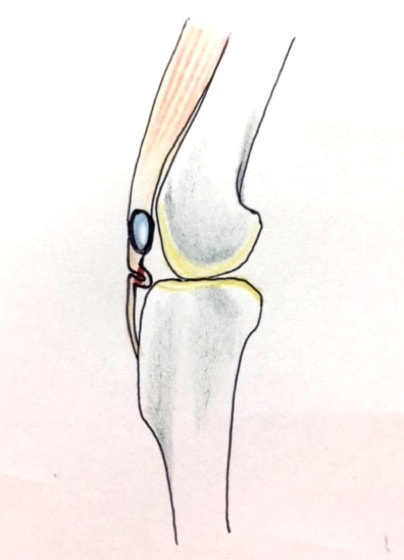

膝蓋骨脱臼は膝関節における膝蓋骨の内外側の脱臼と定義されるが、時として単純な内外の脱臼ではなく、膝蓋骨が大きく前方に浮き上がるように脱臼する場合がある。特にトイプードルやポメラニアンといった犬種に多く認められる。

内側脱臼に加えて前方への浮き上がりを矯正する為に、従来より脛骨粗面転移により膝蓋靭帯を外方と下方に引っ張り、固定する方法を選択する。膝蓋骨の前方への浮き上がりが軽度の場合は、従来法ではなく関節包の縫縮で対応していた。しかし、一部の症例で膝蓋骨の動きが悪くなり伸展機構が円滑に機能せずロボット様歩行になるケースがあった。

その為、膝蓋靭帯自体を縫縮する方法を採用した。この方法により、膝関節の伸展機構を妨げず膝蓋骨の軽度の浮きを矯正することが可能となった。